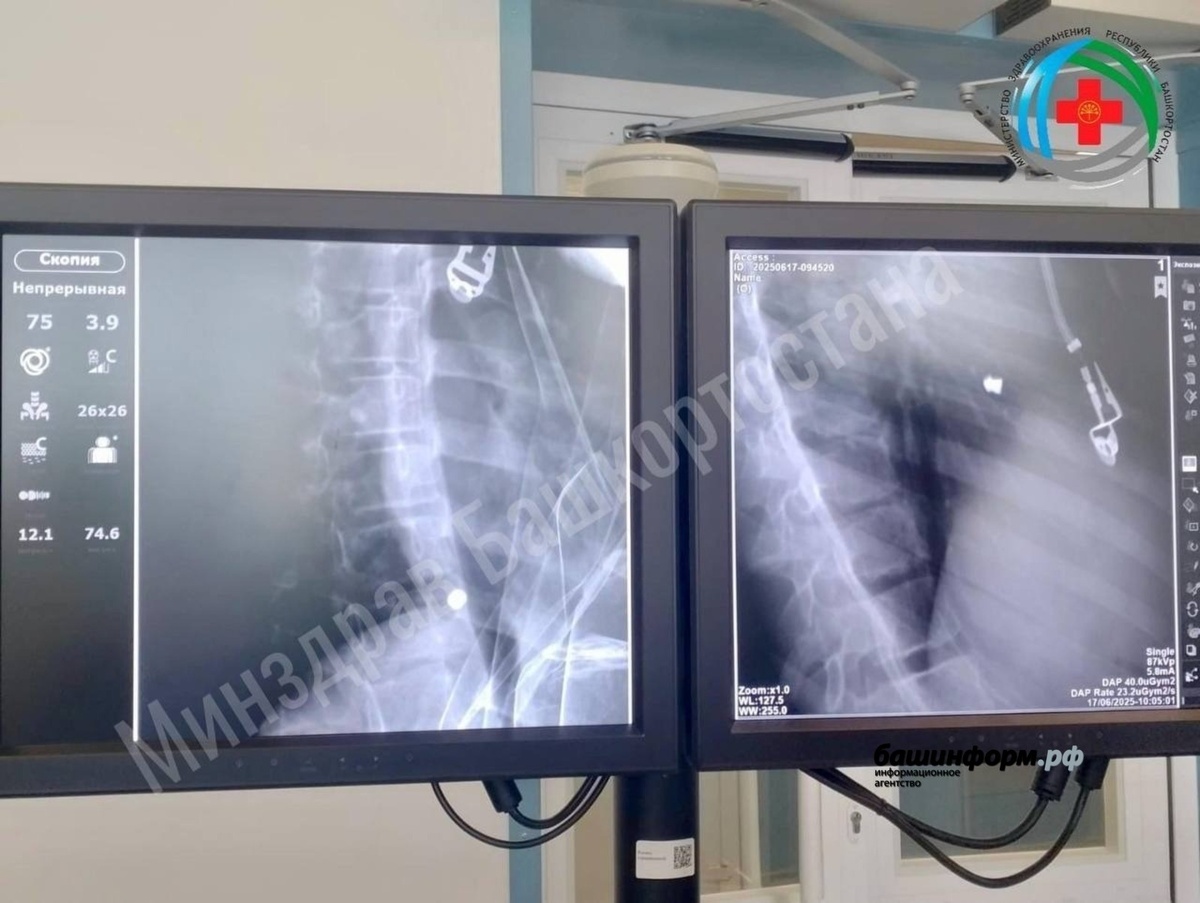

Ранее сообщалось, что девочка пострадала в результате несчастного случая. Инцидент произошёл в Иглинском районе. Пострадавшую в тяжёлом состоянии доставили в Республиканскую детскую клиническую больницу с проникающим ранением сердца и повреждением лёгкого. Девочка жаловалась на сильную слабость, боли при дыхании и глотании. Врачи экстренно провели сложную операцию — торакотомию, вскрыв грудную клетку и извлек пулю. После успешного вмешательства ребёнка перевели в кардиоцентр, где она продолжает находиться под наблюдением специалистов.